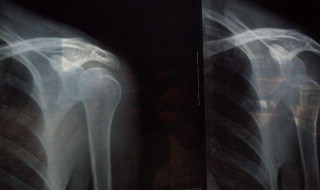

2、肩袖是由一组肌腱组成的,包绕在肱骨头外侧,肩袖损伤,是外力作用所致。分为肩袖腱炎和肩袖撕裂两种情况。其中,绝大多数肩袖损伤是肩袖腱炎,一般及时进行综合治疗即可恢复,而肩袖撕裂则需要进行手术 。